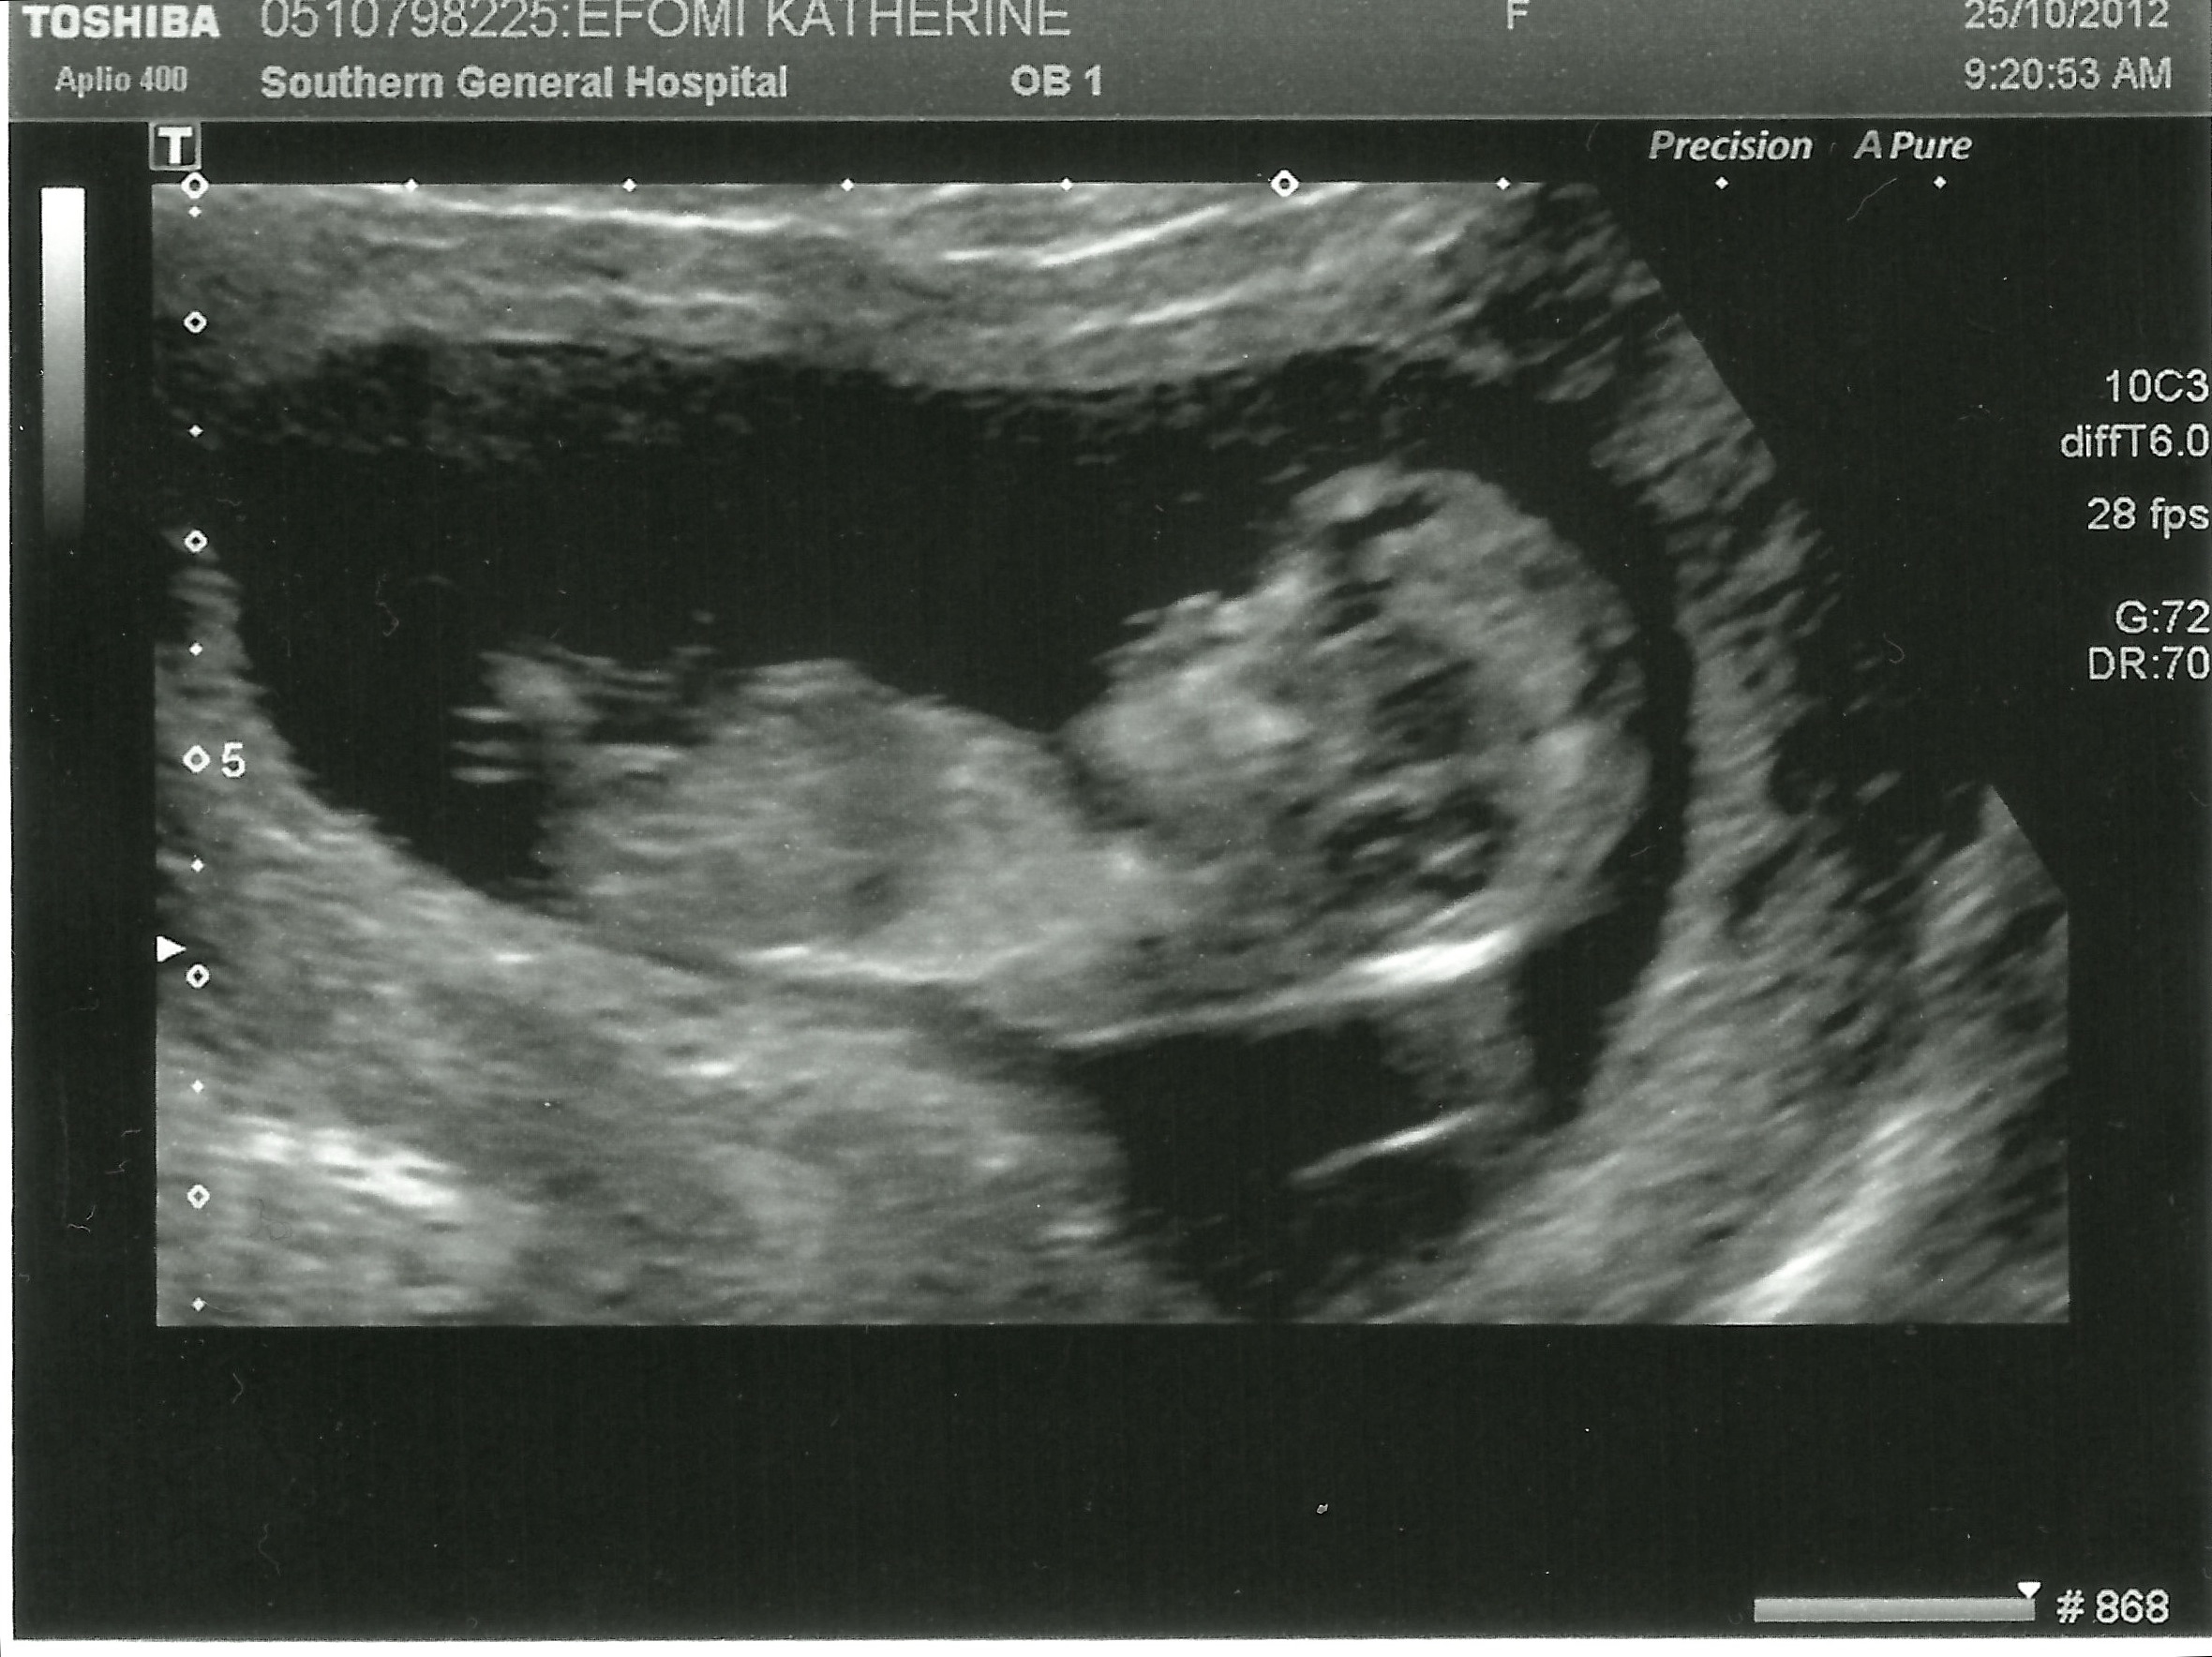

Well slap my wrists and tell me I’ve been a bad’n. I’ve been away for my blog for quite some time now and for this I apologise. But I have an awesome excuse: I was busy making a baby. What can I say? Mini-us is on the way in May! I thank you.

I’m sure Mini is already rocking the beginnings of an afro and was definitely busting some serious hip-hop moves in there during the scan. He/she obviously takes after his/her proud father who, when telling folks we’re expecting, promptly follows the felicitations, back slaps and hand shakes with: “I did it myself”.